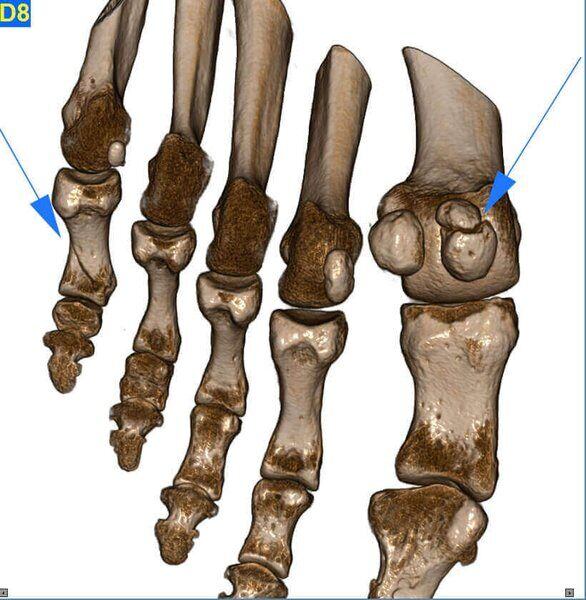

Amputazione dita